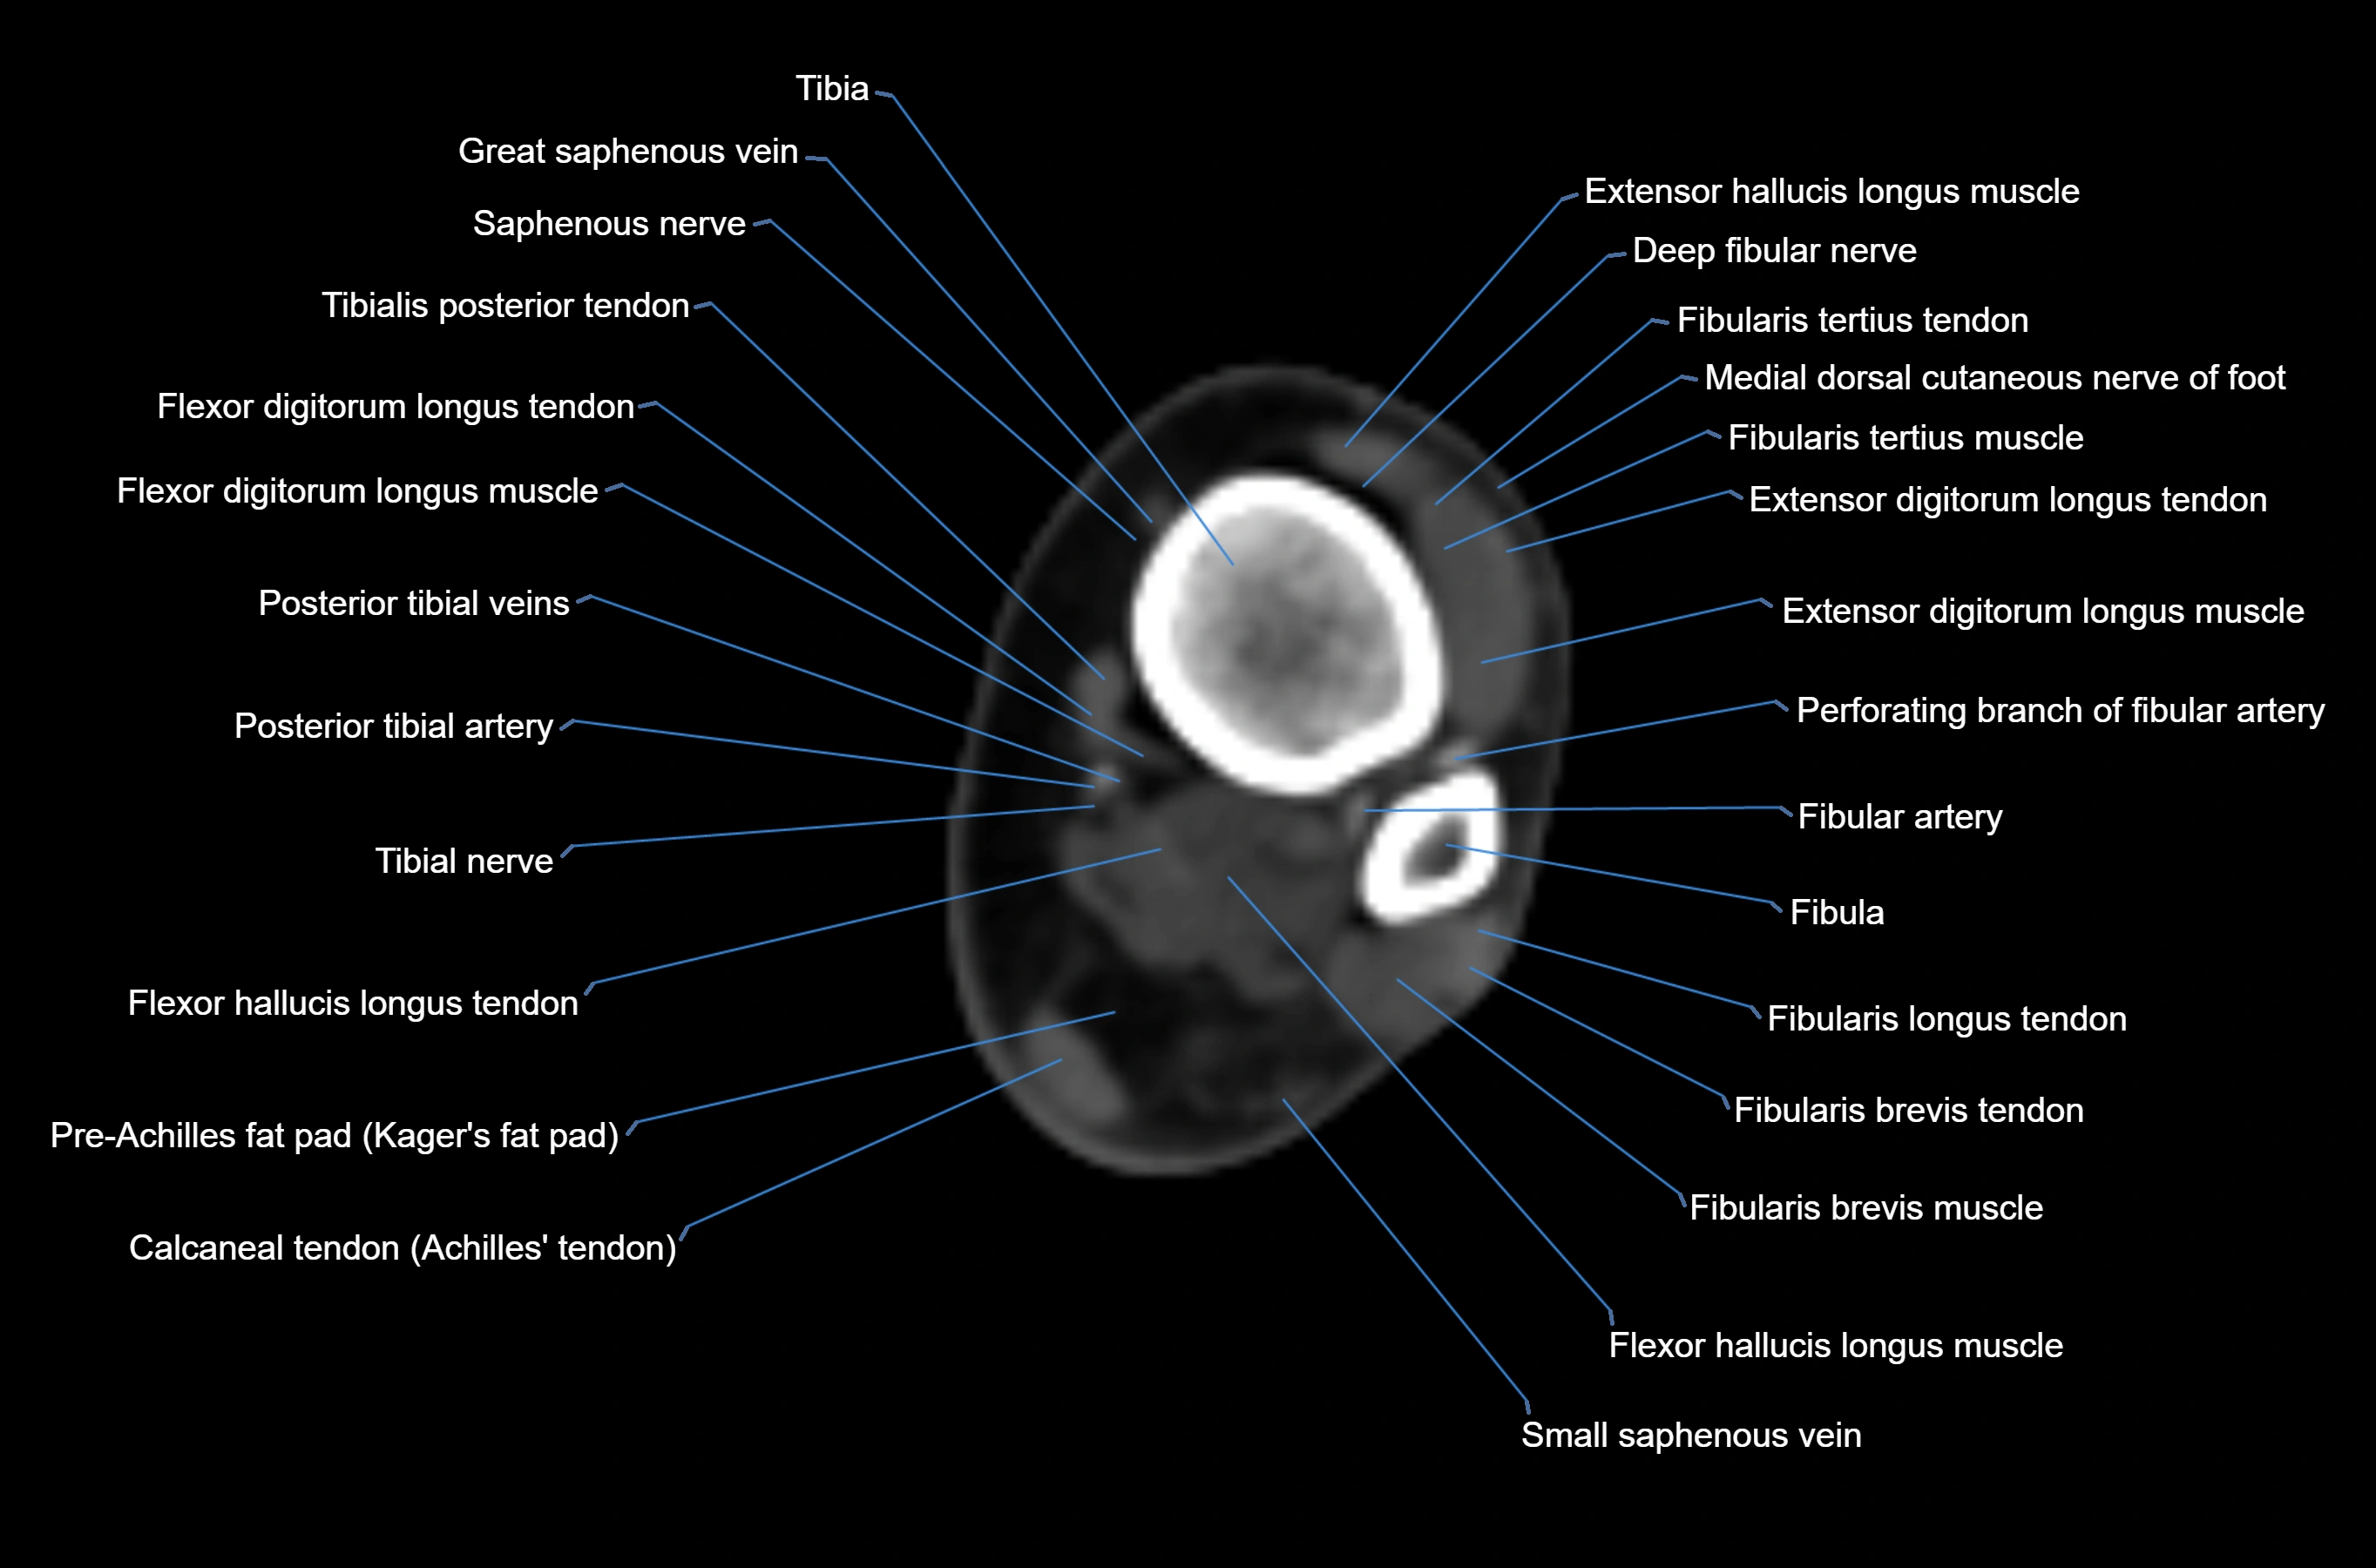

- Fibula

- Fibular artery

- Fibular veins

- Fibularis brevis muscle

- Fibularis brevis tendon

- Fibularis longus muscle (peroneus longus muscle)

- Fibularis longus tendon

- Fibularis tertius muscle

- Fibularis tertius tendon

- Flexor digitorum longus muscle

- Flexor digitorum longus tendon

- Flexor hallucis longus muscle

- Flexor hallucis longus tendon

- Gastrocnemius muscle

- Kager fat pad (pre-Achilles fat pad)

- Posterior tibial artery

- Posterior tibial veins

- Saphenous nerve

- Small saphenous vein

- Tibia

- Tibial nerve

- Tibialis posterior tendon